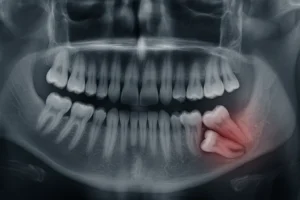

Tedavi süreci kapsamlı bir değerlendirme ile başlar.

MosDent gibi dijital altyapıya sahip merkezlerde 3D CBCT tomografi, intraoral tarama, dijital gülüş tasarımı (DSD) gibi teknolojiler kullanılarak tedavinin en doğru şekilde planlaması yapılır.